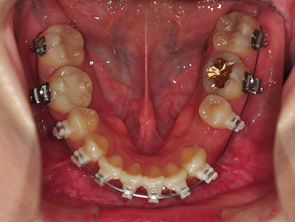

와이어를 꺼낼때느 뭔가 시원한 느낌이 들더라구요 해체하는 기분 ㅋㅋㅋㅋ 와이어 없을때 얼른 사진 하나 찍었어요 쿄쿄

새로 갈아끼운 와이어는 2단계높인 와이어라고 설명해주셨어요 이 와이어는 입안 온도에서 더욱 효과가 잘 일어나는 와이어로 찬 온도에서 그 기능이 저하 될수 있기때문에 얼음물이나 차가운 음료는 많이 마시지 않는게 좋다고 말씀해주셨어요

와이어를 장치들 사이에 끼워넣고 탁탁 장치를 맞출때마다 치아가 하나씩 타이트하게 조이는 느낌이 들어왔어요 이때 어느분은 아프다고 느끼실수도 있겠지만 저는 뭔가 딱! 잡아주는 느낌같았어요 뭔가 배에 복대를 했으때의 느낌이랄까 ,,ㅋㅋ

하악 스크류 진행은 사진에 위치와 각 위치에 대해 설명을 넣어놓은것처럼 앞부분에 스크류를 넣는것이 가장 이상적이지만 치아를 발치한 부분이어서 잇몸이 약해 스크류를 넣기 힘들수도 있다고 하시더라구요 ㅠㅠ 그래서 그다음으로 후보2번째 에 스크류를 넣을 수도 있고 만약 후보2번에 안된다면 입안쪽으로 후보3번 부분에 해야하는데 그쪽은 잇몸을 절제해서 스크류를 진행해야 한다고 하시면서 잇몸 건강하죠~~?? 하시는 의사 선생님 후엉!! 제발~!!!!! 후보1번에 스크류 할수있었으면 좋겠어요 ㅠㅠㅠ